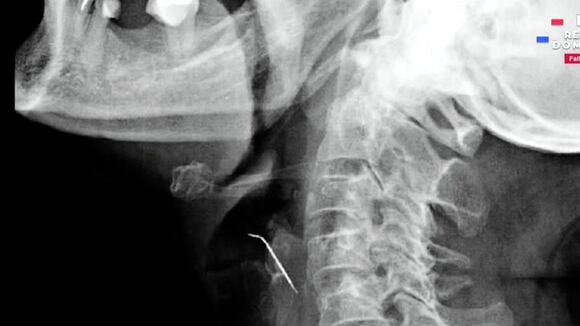

Fue así que los especialistas le realizaron exámenes y una tomografía que demostraron que un objeto metálico atravesaba la arteria importante que lleva irrigación al cerebro.

La cirugía duró aproximadamente 3 horas; luego de ubicar el clavo de 5 centímetros. Se realizó una delicada disección del área afectada con el riesgo de que algún coagulo se forme y llegue al cerebro.